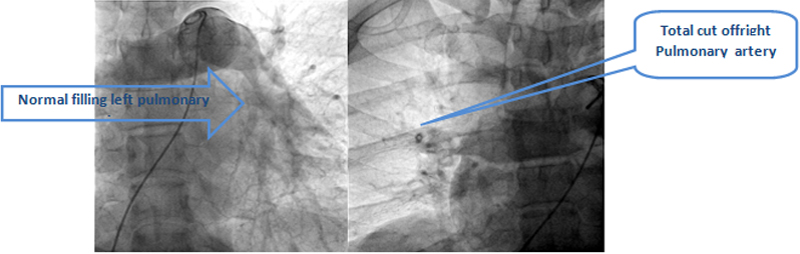

Diagnosis was confirm by pulmonary angiography which revealed total cut off of right side of pulmonary artery due to large thrombus and complete occlusion of his brachial-axillary artery by large thrombus. Looking to literature and available scientific evidence, the preferred treatment of choice of the patient with massive pulmonary embolism is systemic thrombolysis.

Risk of thrombolysis includes intracranial bleeding and bleedings from other part of body. He responded well with the treatment and he started maintaining basic oxygen level without oxygen support from the next day onward. His pulse on the right side of the hand came back and he started feeling comfortable from the next day morning. He had little bleeding and oozing from the angiographic puncture site on the right leg, otherwise no bleeding from anywhere.